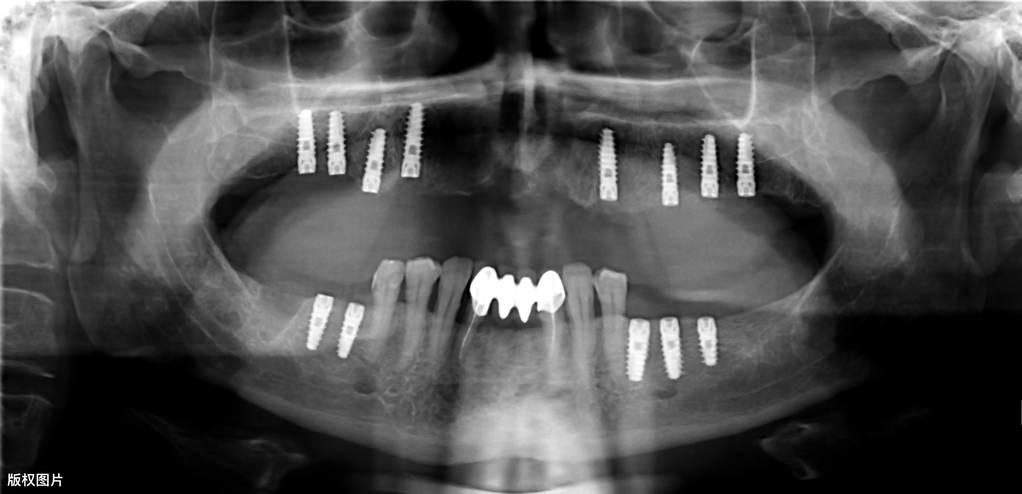

種植牙的一般流程● 術(shù)前檢查:術(shù)前需要拍攝X線片、頜骨CT等,對缺失牙的部位及整個口腔狀況進行系統(tǒng)性檢查。符合種植的適應(yīng)癥,排除禁忌癥后,根據(jù)患者的具體情況制定種植調(diào)節(jié)方案,預(yù)約種植手術(shù)時間。

● 垂直方向的骨吸收不超過種植手術(shù)完成時植入在骨內(nèi)部分長度的1/3(采用標(biāo)準(zhǔn)投照方法X光片顯示)。醫(yī)學(xué)教育|網(wǎng)搜集橫行骨吸收不超過1/3, 種植體不松動。

● 放射學(xué)檢查,種植體周圍骨界面無透影區(qū)。